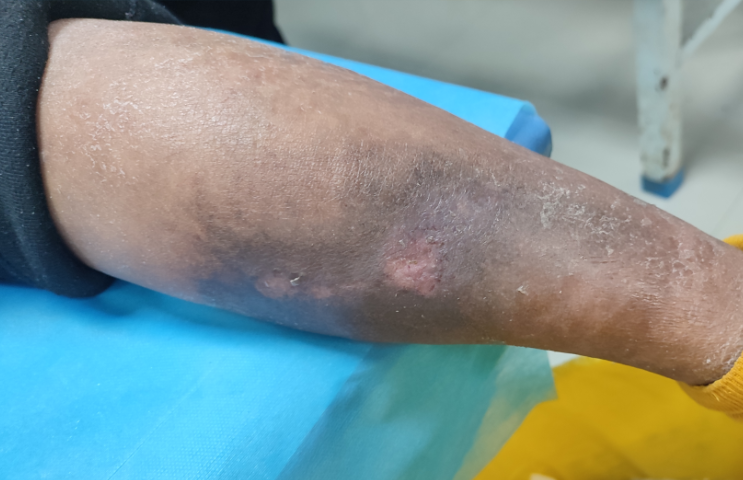

入院时创面

专科检查提示,患者右足背动脉搏动减弱,温痛觉下降,右小腿及腿腹区域皮肤大面积暗黑、皮温偏低。创面范围约10×19cm,形态不规则,向腘窝方向延伸,深度已达肌层,创腔基底暗红。由于下肢静脉疾病本身即严重影响组织修复能力,叠加糖尿病所致微循环障碍与免疫功能下降,使得该创面愈合极为困难,感染风险显著升高。面对这一复杂病例,我院外科团队迎难而上,凭借丰富的创面管理与血管外科经验,制定了周密的治疗计划。